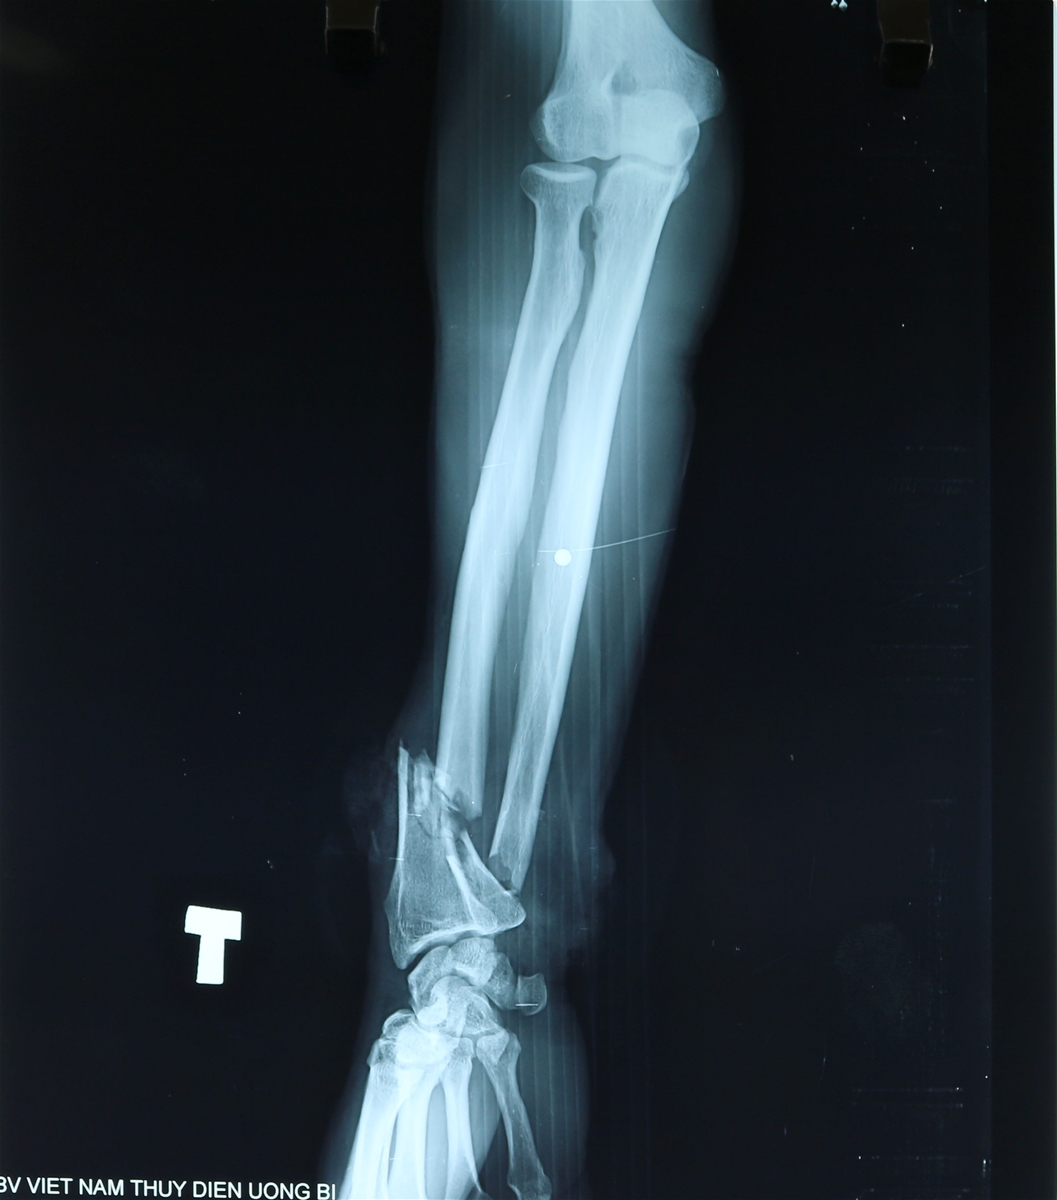

| Hình ảnh cẳng tay gần như đứt lìa của anh Sơn |

Anh Sơn nhập viện trong tình trạng vết thương phức tạp: dập nát 1/3 dưới cẳng tay, đứt da tay toàn bộ vùng cẳng tay, mất nhiều máu, gãy xương, đứt động mạch, đứt gân cơ.

BSCKI. Nguyễn Đức Hoành - Trưởng khoa Phẫu thuật Can thiệp tim mạch & Lồng ngực cho biết người bệnh Sơn nhập viện trong tình trạng rất nặng, do đứt động mạch, đứt da toàn bộ vùng cẳng tay, mất nhiều máu, nếu không được tiến hành phẫu thuật cấp cứu kịp thời thì nguy cơ người bệnh phải cắt bỏ cẳng tay và nguy hiểm hơn có thể đe dọa đến tính mạng.